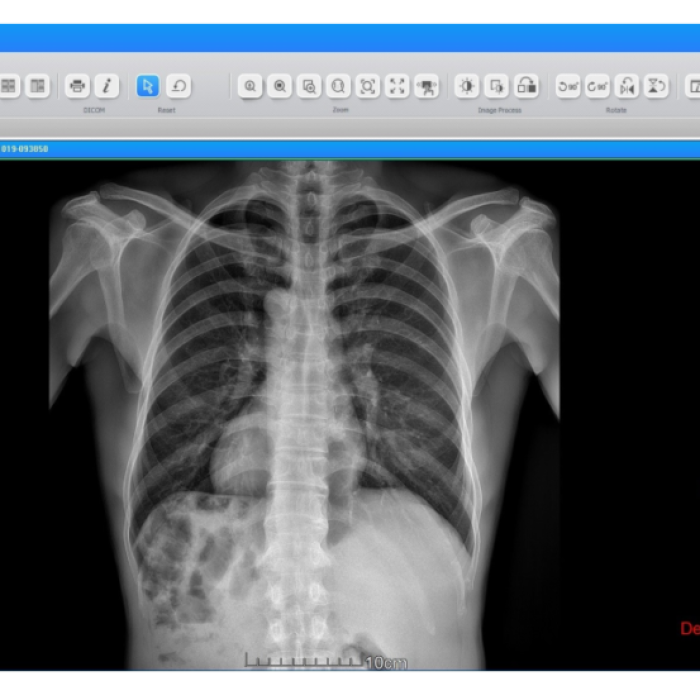

Radiography

Radiography

🔹 Simple workflow

🔹 Emergency exam

🔹 Image preview

🔹 Fast image processing time (<0.8 sec)

🔹 Advanced image processing